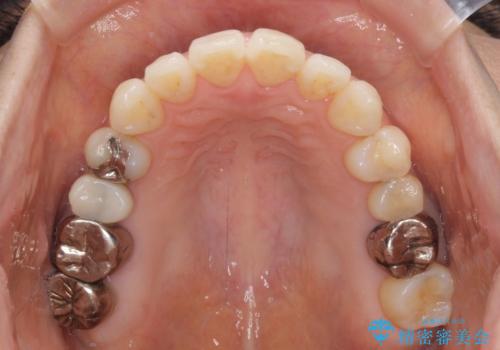

- 捻れた前歯と目立つ銀歯を気にして来院された患者様です。

歯列不正は軽微であったため、インビザライン・ライトにて改善することとしました。

左下大臼歯は根管治療が必要であったため、矯正治療前に根管治療を行い、その後矯正治療を行うこととしました。

矯正治療後には期にある銀歯を全てセラミッククラウンなどで補綴治療することとしました。

インビザライン・ライトによる矯正治療であったので、時間をかけずに治療を終えることができました。

口を開ける度に目立っていた銀歯もセラミックで自然な口元の印象となりました。